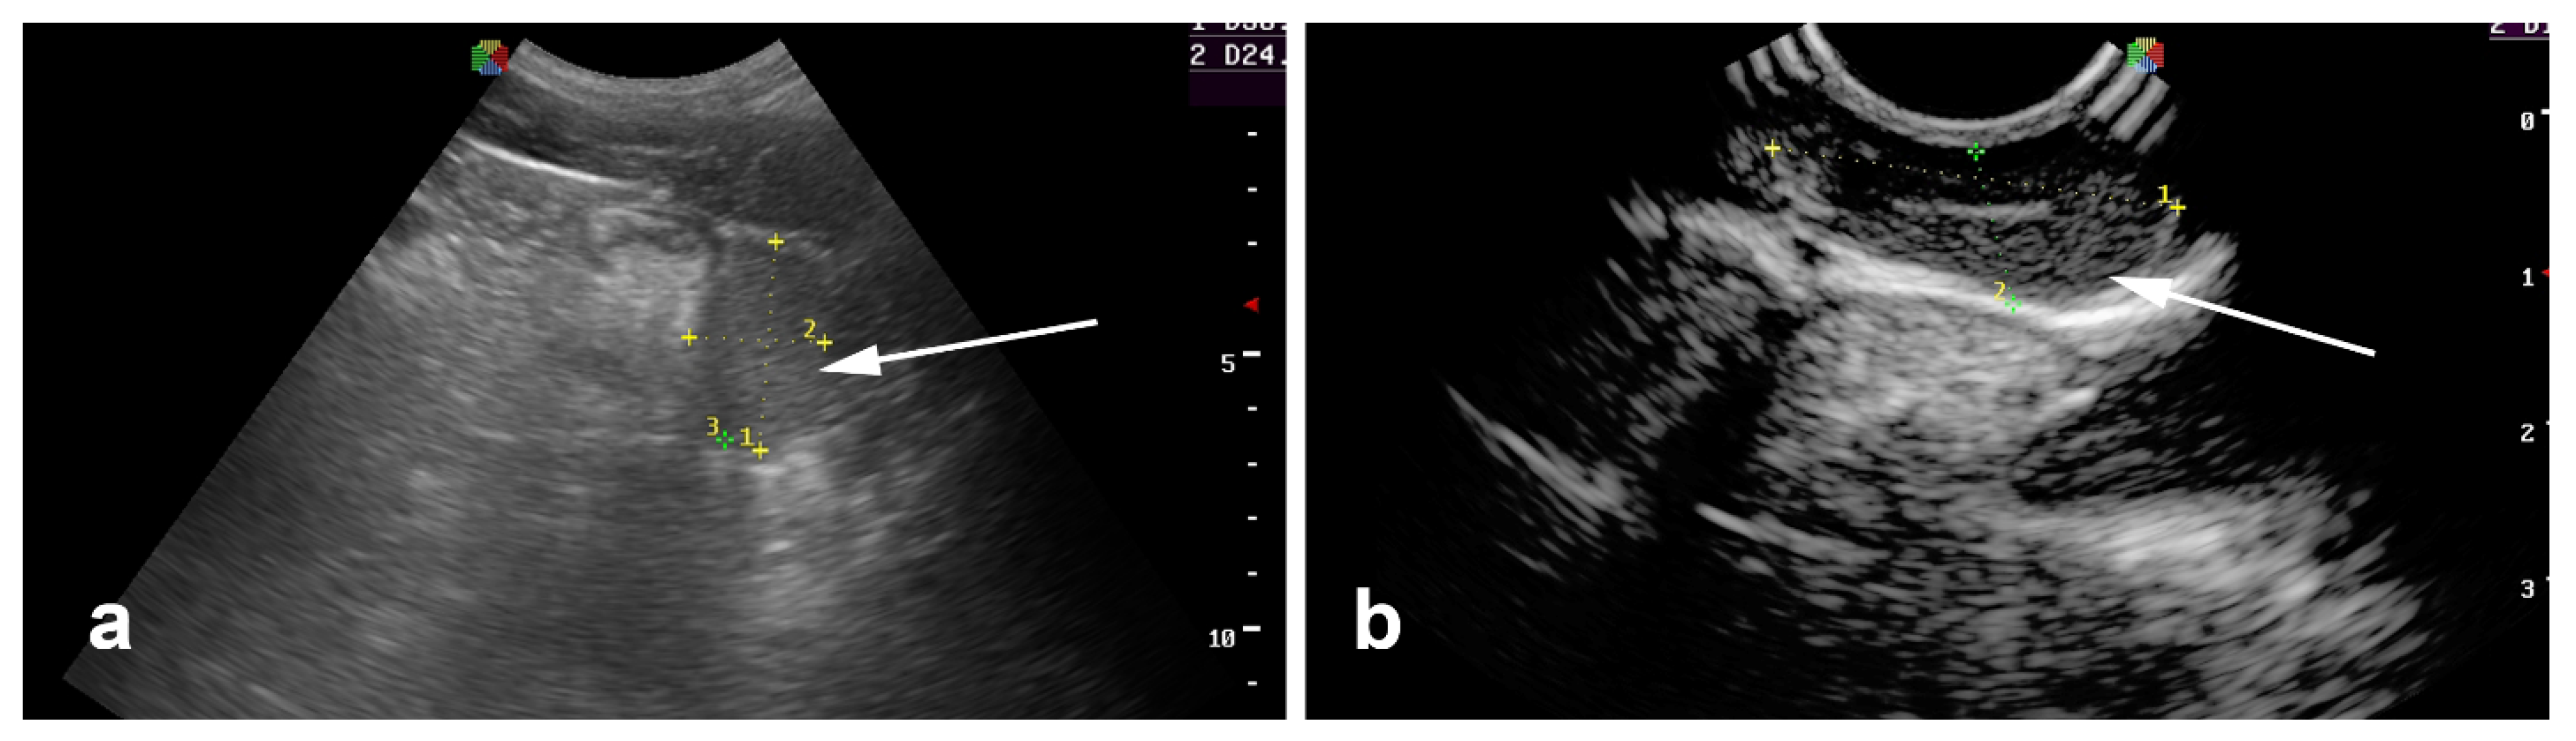

5.3. Varicocele

5.4. Scrotal and Testicular Tumors